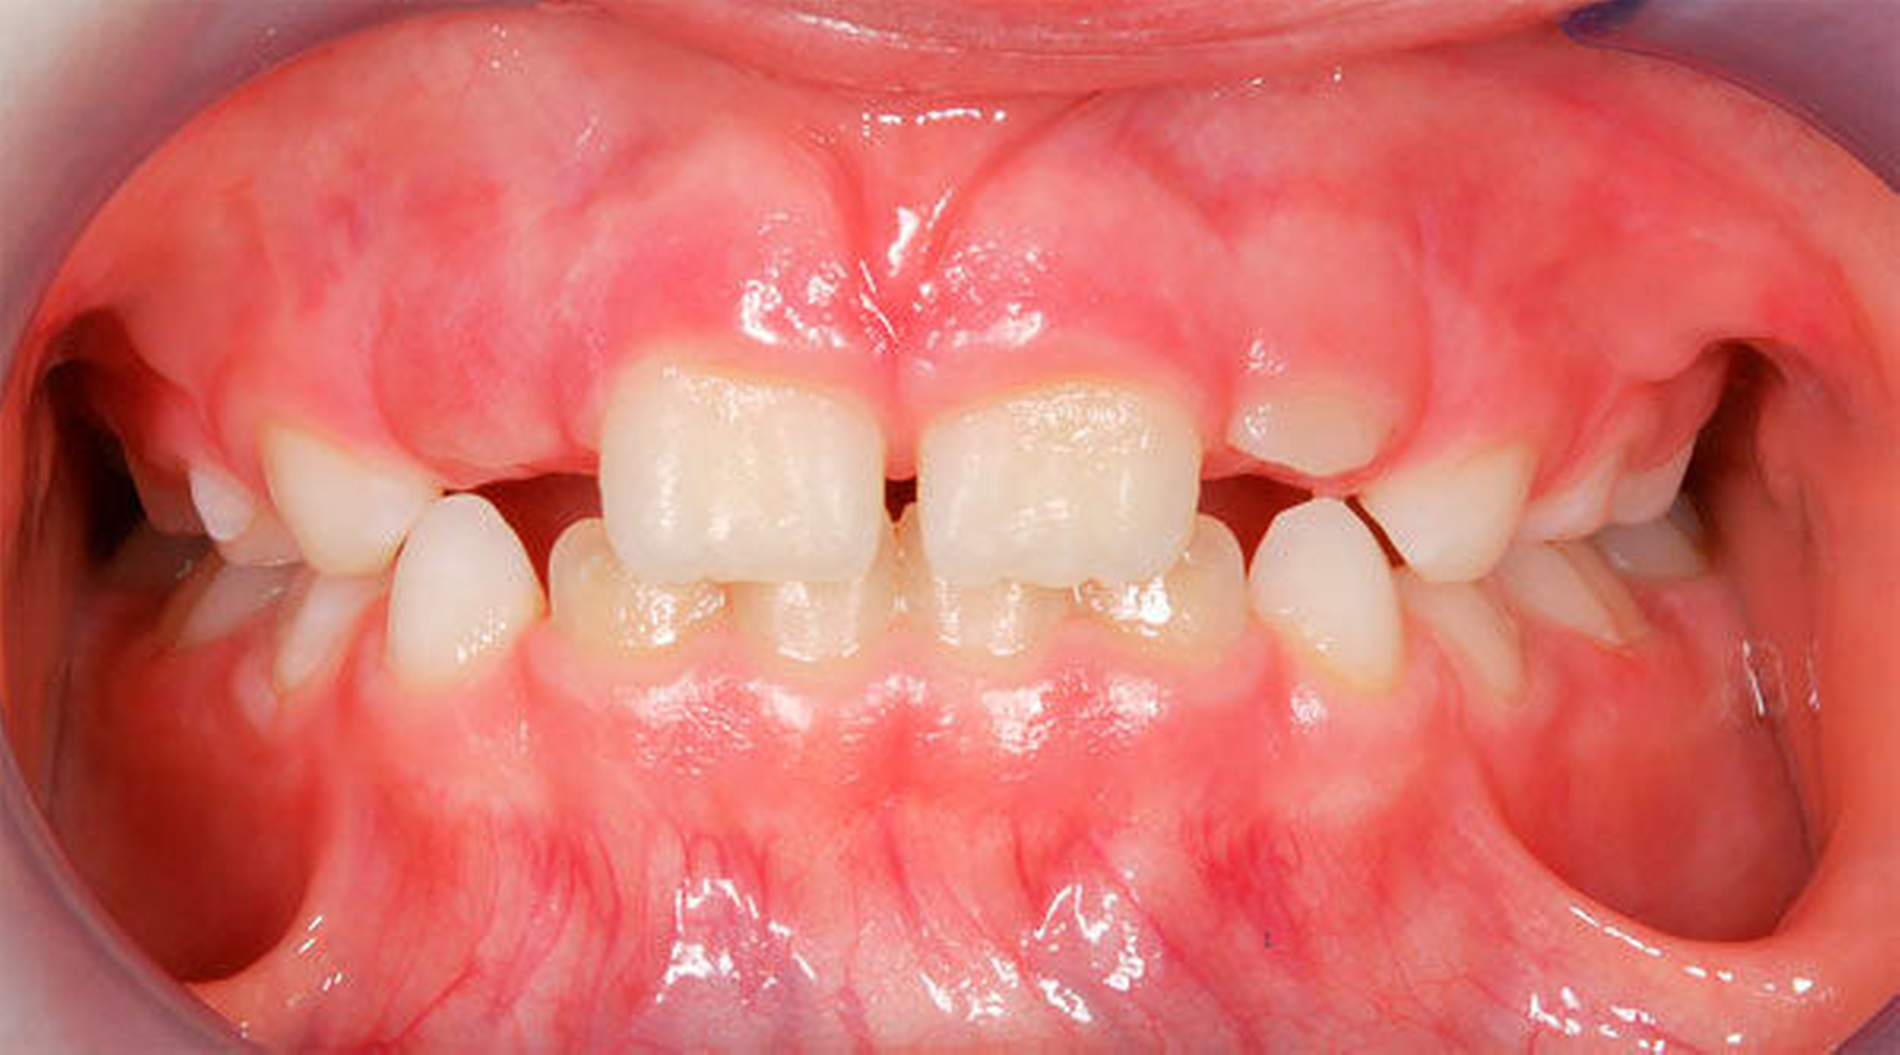

Ausgeprägte Zahnfehlstellungen und Gebissanomalien zeigen sich im reinen Milchgebiss deutlich seltener als im Wechsel- oder im permanenten Gebiss [Schopf, 2003]. Dennoch sollten bereits in dieser frühen Phase beispielsweise die Platzverhältnisse für die später durchbrechenden Zähne beurteilt werden. Im Säuglingskiefer liegen die Zahnkeime der Milch-Inzisiven zunächst in einer sagittalen Staffelstellung [van der Linden, 1980]. Die mit dem Durchbruch der Milchzähne einhergehende Bildung des Alveolarfortsatzes und die wachstumsbedingte Vergrößerung der Zahnbögen führt meist zu einer lückigen Stellung der Milchschneidezähne [Sillman, 1964] (Abbildung 1). Diese Lücken tragen dazu bei, den deutlich breiteren bleibenden Nachfolgern eine regelrechte Einordnung in den Zahnbogen zu ermöglichen [Moyers, 1976; Leighton, 1978]. Ein „schönes“, lückenloses Milchgebiss oder gar Engstände in der Front sind ein Alarmsignal im Hinblick auf spätere Platzprobleme für die bleibenden Zähne [Leighton, 1969]. Bei diesen Patienten ist eine intensive Überwachung während des Zahnwechsels der permanenten Inzisiven ratsam, um gegebenenfalls rechtzeitig Platz schaffende Maßnahmen einleiten zu können.